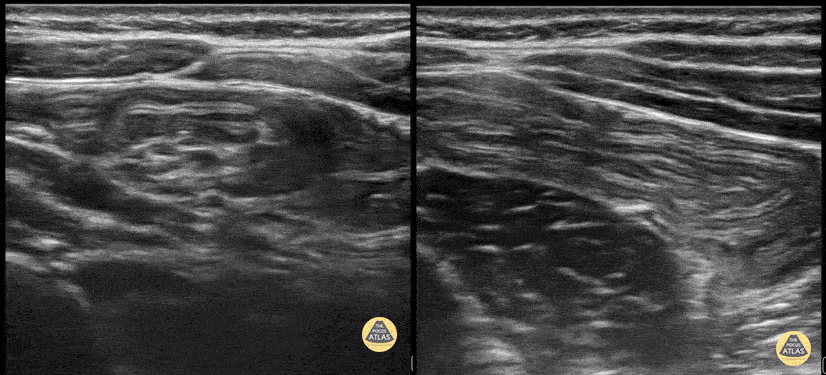

Toddler with colicky abdominal pain. LUQ with ileo-ileal intuss. Note the smaller size and active peristalsis of the intuss. Contributor: Matthew Moake, MD PhD